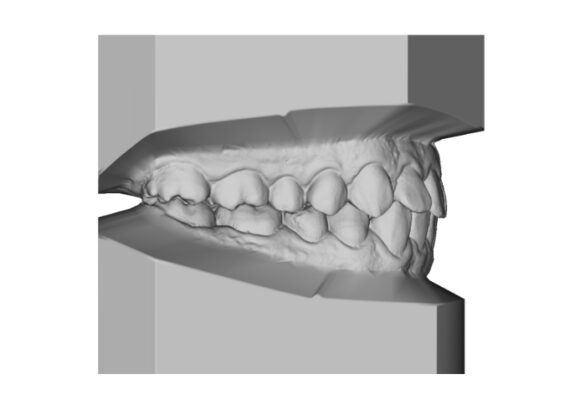

El escaneo dental es un dispositivo digital utilizado para capturar impresiones tridimensionales de la boca del paciente.

Este tipo de escaneo permite recrear la dentadura con una precisión que supera con mucho las muestras tomadas con materiales de impresión tradicionales.

• Réplica exacta de las estructuras dentales y tejidos adyacentes del paciente.

• La ventaja es que su consulta se actualiza dejando atrás modelos de yeso que se rompen o maltratan y que además debe de almacenar. Le damos la alternativa de almacenarlos digitalmente teniéndolos virtualmente en su computadora y si requiere imprimirlos podemos realizarlo en el momento que necesite.

• Los escaneos son considerados tan precisos si no más exacto que los moldes de yeso. El proceso de escaneo es más cómodo para pacientes especialmente con reflejo nauseoso.

• Comodidad para pacientes con reflejos de nauseas.